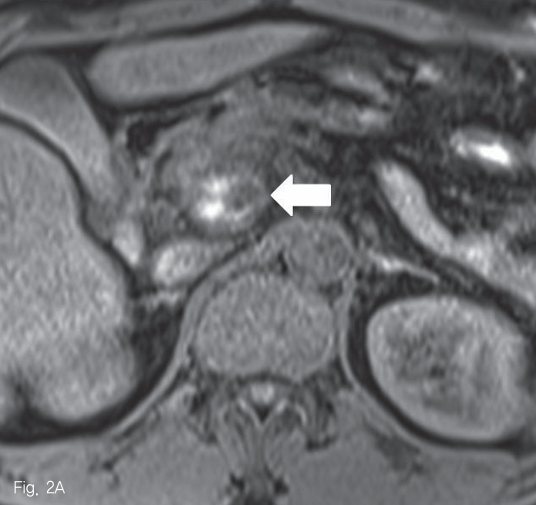

초음파 검사에서 췌장 두부에 약 2.5cm 크기의 종괴가 있었다 (Fig. 1). 췌장 자기공명영상에서 종괴는 T1-weighted image에서 다양한 신호강도를 보였고, T2-weighted image 에서는 저신호강도를 보여 다양한 단계의 출혈을 포함한 병변으로 생각하였다 (Fig. 2A-B). 조영 증강 자기공명영상 및 조영 증강 복부 전산화단층촬영에서 종괴의 내측으로 혈관과 비슷한 조영 증강을 보이는 1cm 크기의 병변이 보여 가성동맥류로 진단하였다 (Fig. 2C-D).

Fig 2A

Pancreatic MRI reveals a mass in pancreatic head. It shows heterogeneous signal intensity in T1-weighted image (A, arrow) and low signal intensity in T2-weighted image (B, arrow).

Fig 2C

Contrast-enhanced MRI (C) and CT (D) images reveal well-enhancing nodular lesion (curved arrows) in medial aspect of the pancreatic mass (arrow).